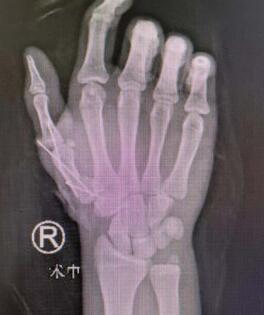

术前

急诊科的值班人员接到患者后,立即电话通知了手外四病区的医疗团队,同时开通绿色通道。专科检查显示患者右拇指完全离断,右桡骨远端及尺骨茎突骨折,右手第2掌骨基底部骨折,右腕头状骨及小多角骨骨折。

内固定

术后即刻

8月8日,右拇指顺利成活后,郑主任手术团队又为患者进行了右桡骨骨折切开复位内固定术。术中充分暴露桡骨骨折断端并复位,予克氏针交叉固定,放置钢板使用螺钉固定。